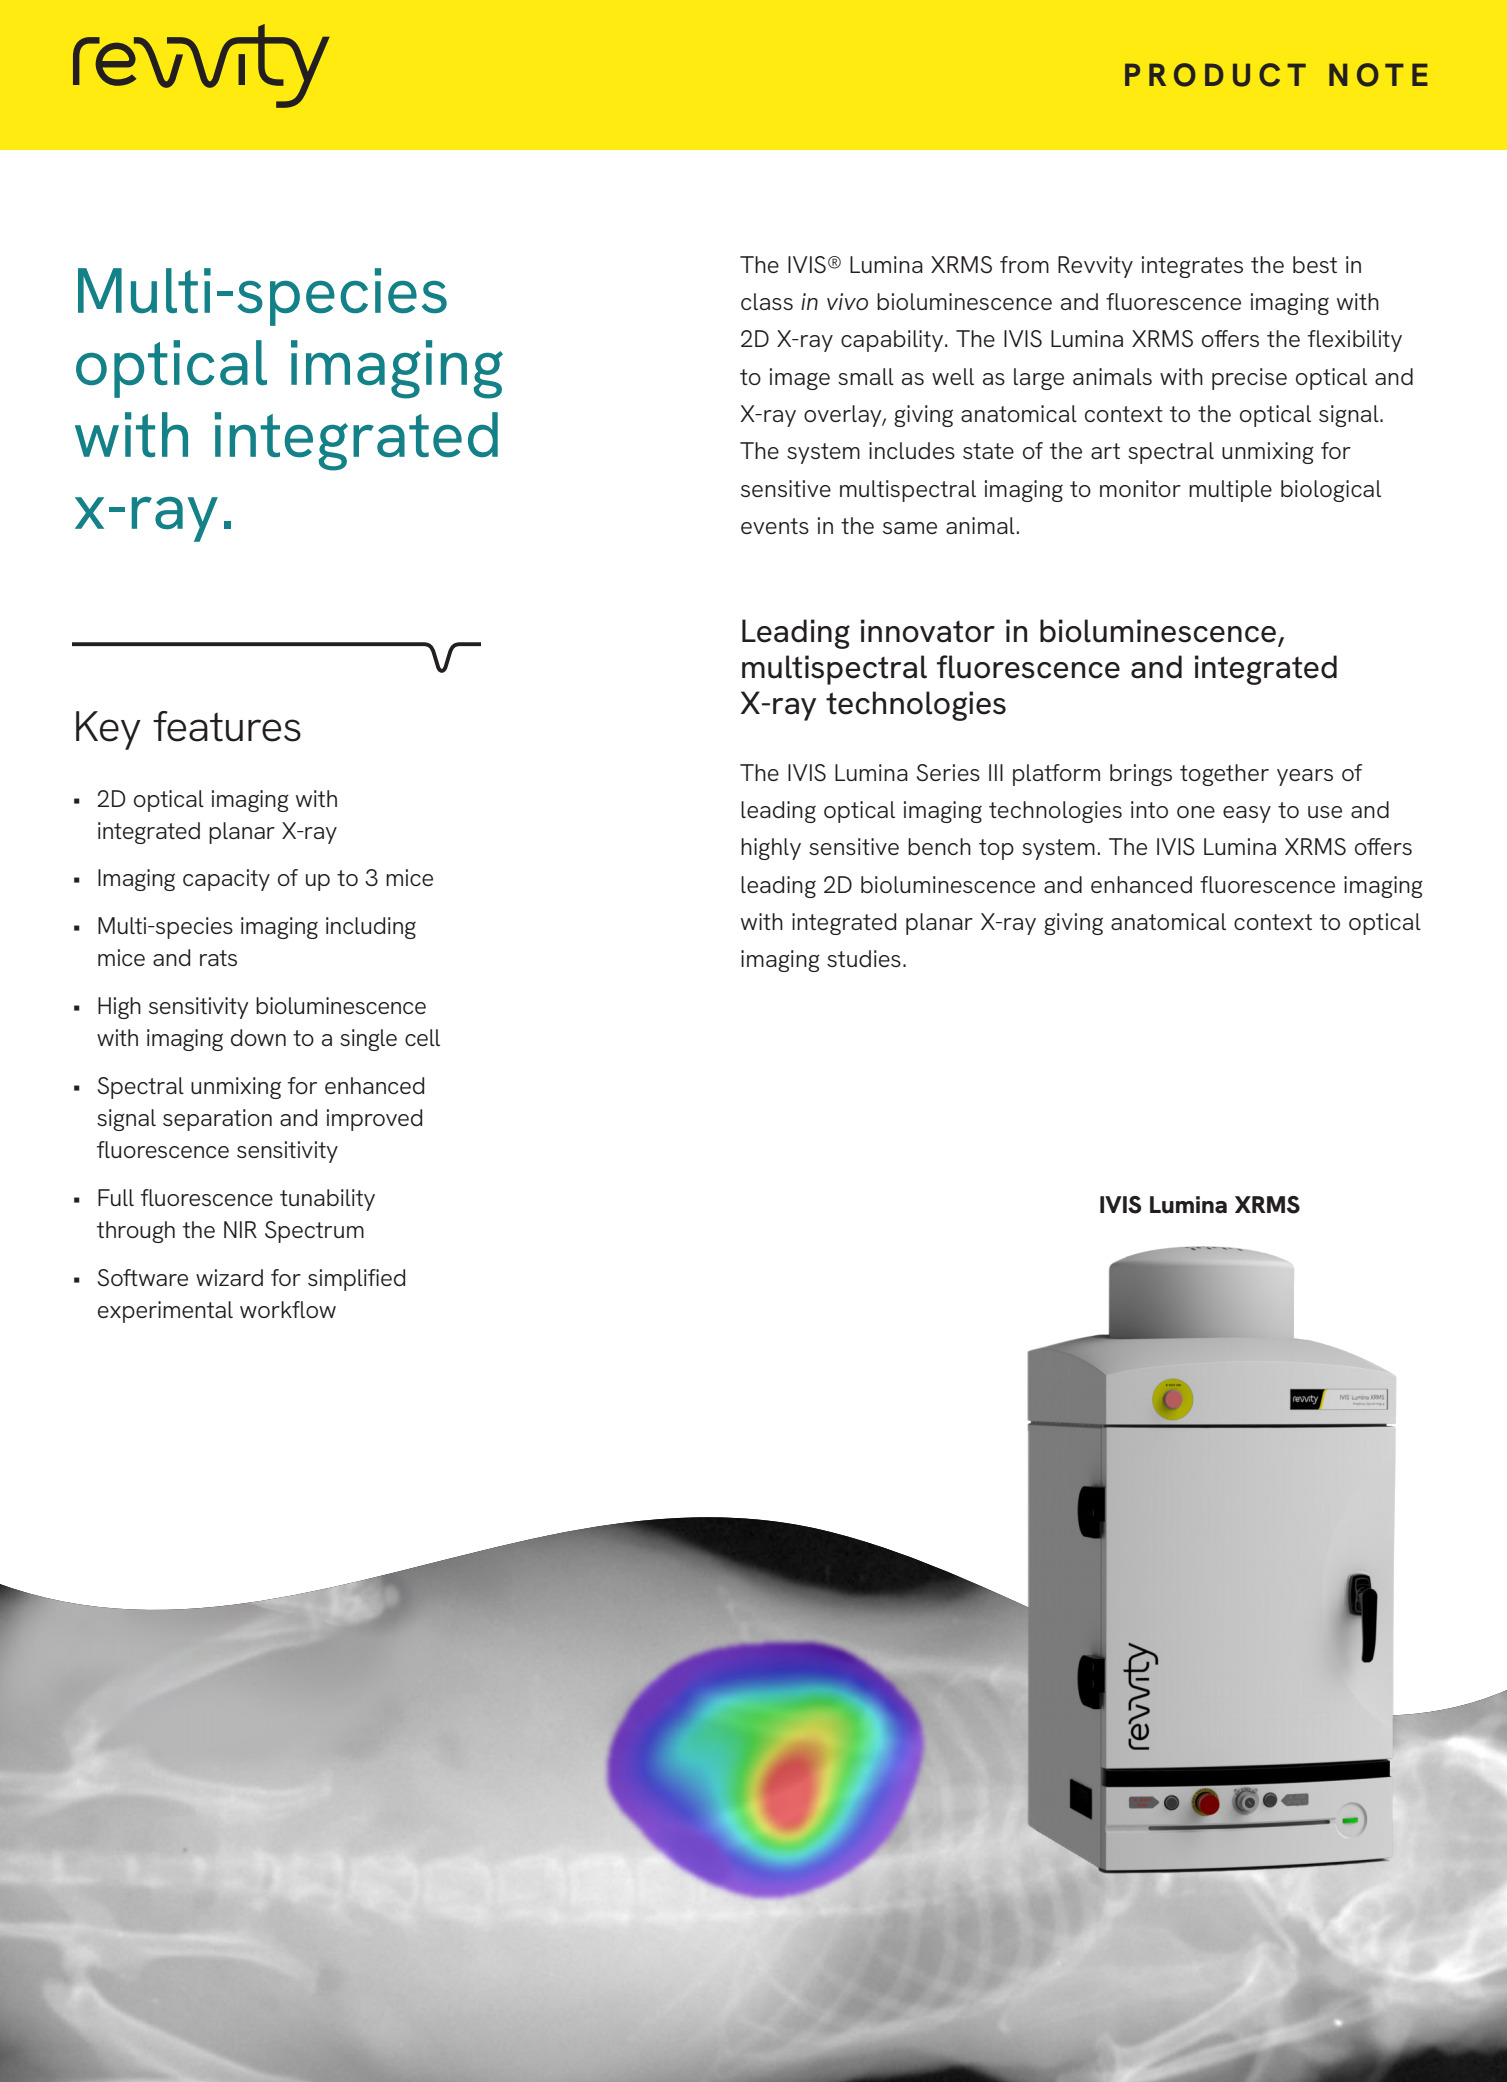

IVIS Lumina XMRS

IVIS Lumina XRMS

IVIS Lumina XRMS

Opis

Aparat do przyżyciowego obrazowania zwierząt laboratoryjnych IVIS Lumina XRMS przeznaczony jest do badań dwuwymiarowych z zastosowaniem obrazowania luminescencyjnego, fluorescencyjnego oraz obrazowania promieniowania Cerenkova, a także RTG. Umożliwia to uzyskiwanie złożonych obrazów sygnałów fluorescencyjnych lub /i luminescencyjnych w kontekście obrazu RTG budowy anatomiczne zwierzęcia. Zaawansowana optyka, duży wybór filtrów wzbudzeniowych i emisyjnych, technologia Spectral Unmixing oraz wyposażenie dodatkowe takie jak dedykowany system anestezji gwarantują szerokie spektrum zastosowań aparatów IVIS Lumina XMRS zarówno w badaniach nad nowymi lekami, komórkami macierzystymi, rozwojem stanu zapalnego jak i w badaniach nad terapiami spersonalizowanymi. Standaryzacje badań gwarantuje możliwość absolutnej kalibracji zgodnej ze standardami NIST.